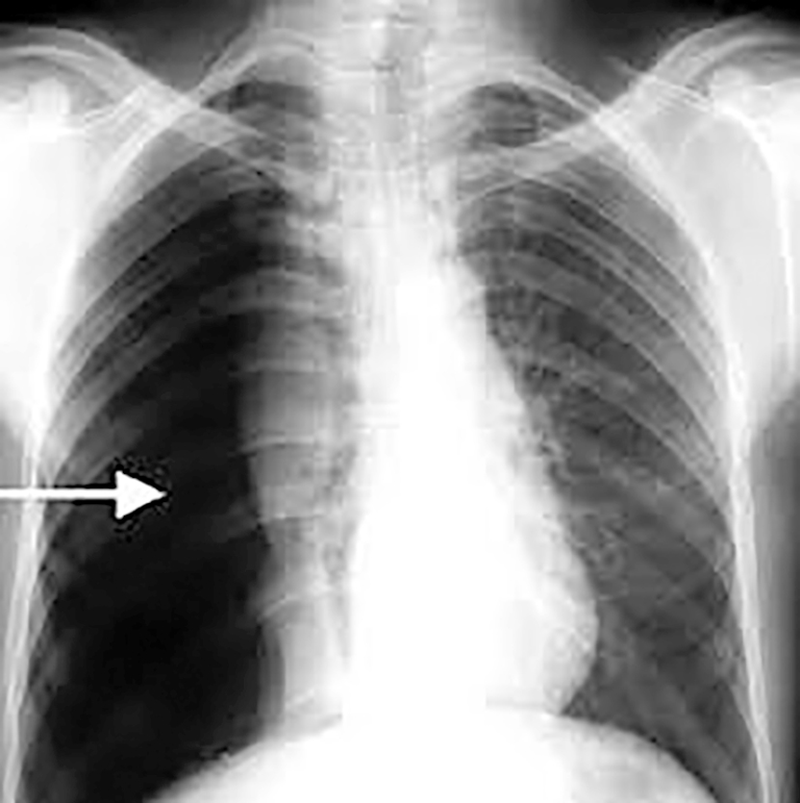

Tràn khí màng phổi tự phát là gì? Nguyên nhân gây ra? Cách điều trị

Khi khí xuất hiện đột ngột trong khoang màng phổi do các tổn thương bệnh lý của phổi và màng phổi gây ra thì được gọi là tràn khí màng phổi tự phát.

Tràn khí màng phổi có thể tự do hoặc đóng ngăn, do đó phổi sẽ ép lại ở những mức độ khác nhau. Chính vì vậy gây hạn chế thông khí và rối loạn tuần hoàn do trung thất và tim bị đẩy sang bên đối diện. Tràn khí màng phổi tự phát không phải là một bệnh mà là một hội chứng do nhiều nguyên nhân gây nên.